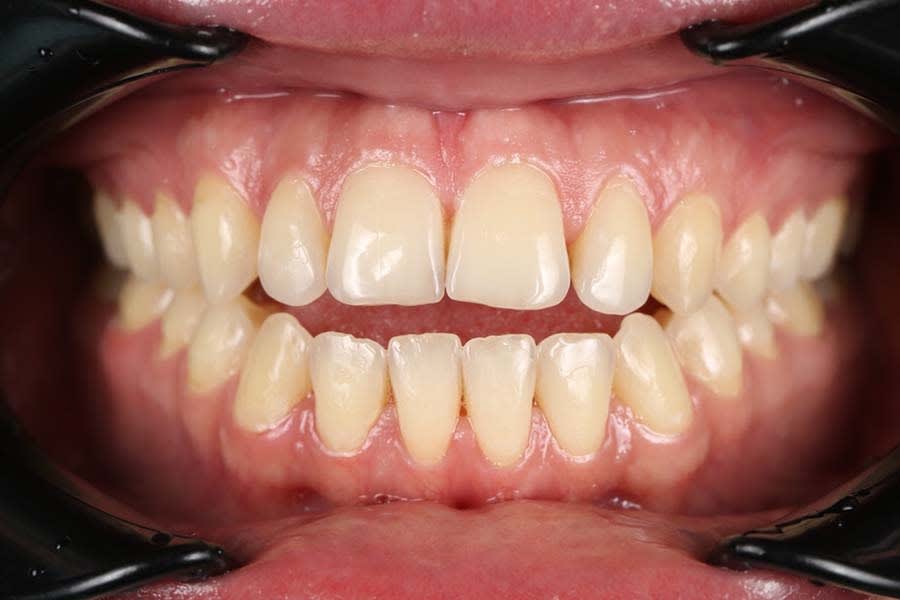

A 26-year-old female patient presented with complaints of unsatisfactory smile esthetics, difficulty biting food, and speech issues. Her medical history was unremarkable. Clinical examination revealed an anterior open bite, mild chronic generalized periodontitis, and impacted third molars in the third and fourth quadrants. Accurate diagnosis of occlusal issues was critical in the treatment planning.5

A panoramic radiograph was recorded (Figure 1), followed by a clinical examination (Figure 2). A jig was fabricated to stabilize centric relation (CR) (Figure 3), and jaw movements were analyzed using a virtual articulator in CAD software (exocad, exocad.com) (Figure 4). Digital wax-ups and guides were employed to enhance surgical and restorative accuracy.6